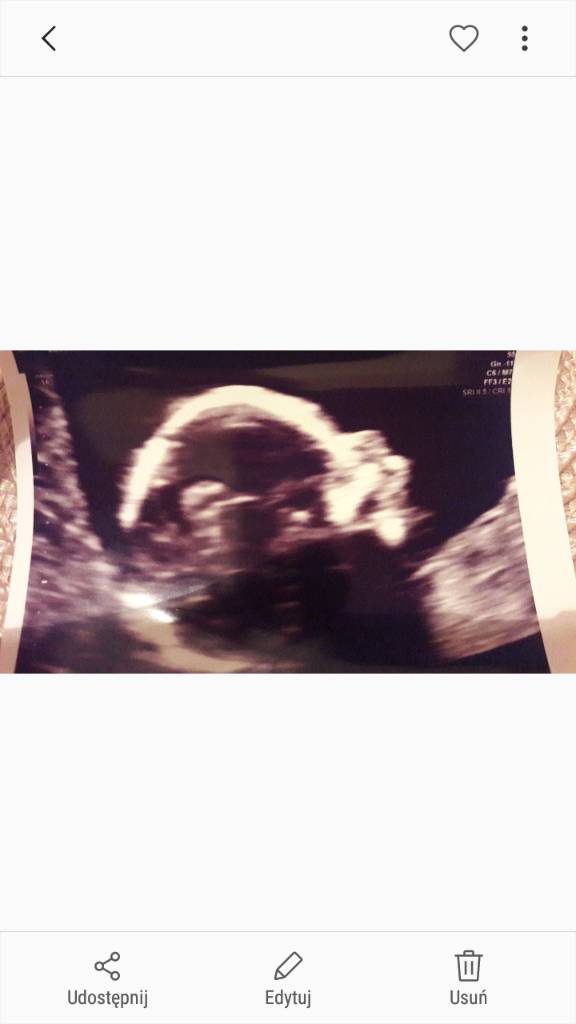

Hej, ja już po wizycie. Prawdopodobnie (lekarz był bardzo mocno przekonany przy ferowaniu swego osądu) będą chłopaki.

Szczerze powiedziawszy zbił mnie z pantałyku, bo kilka razy słyszałam, że ma być parka ale jestem szczęśliwa. Serduszka pięknie biją, wszystkie narządy są widoczne.

Justynko raz jeszcze twierdzę że widok jest cuuudowny i wzruszający [emoji7][emoji173][emoji4]

@Justin87 piękne widoki zarażam się na maksa❤️❤️❤️❤️❤️❤️